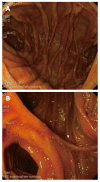

Endoscopic retrograde cholangiopancreatography (ERCP) in patients with surgically altered anatomy is challenging. Several operative interventions of both the gastrointestinal tract and the biliary and/or pancreatic system lead to altered anatomy, rendering ERCP more difficult or even impossible with a conventional side-viewing duodenoscope. Adapted endoscopes are available to reach the biliopancreatic system and to perform ERCP in patients with altered anatomy. However, both technical difficulties and complications determine the procedure's success. Different technical approaches have been described and are highly dependent on local expertise and endoscopic equipment. Standardized practical guidelines are currently unavailable. This review focuses on the challenges encountered during ERCP in patients with altered anatomy and how to deal with them. The first challenge is reaching the papilla or the bilioenteric/pancreatoenteric anastomosis in the patient with postoperative altered anatomy. The second challenge is the cannulation of the biliopancreatic system and performing all conventional ERCP interventions and the third challenge is the control of possible complications. The available literature data on this topic is reviewed and illustrated with clinical cases.